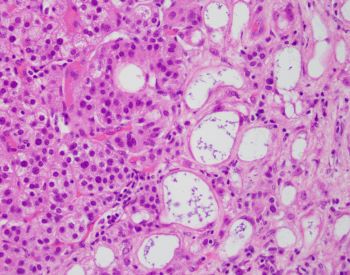

On histologic examination, this nodule consisted of adrenal cortical adenoma admixed with canalicular and tubular (gland like) structures. Tubular structures were typically characterized by flat cells. Some of the cells exhibited vacuolated cytoplasm resembling signet ring cells.

The tubular and canalicular structures were positive for calretinin, and adrenal cortical adenoma was negative for calretinin.

Adenomatoid tumors are positive for mesothelial markers (calretinin, HBME-1), cytokeratins and thrombomodulin.

Complex tubules with gland like appearance are cell groups with round intracytoplasmic vacuoles, vesicular nucleus and small nucleolus may simulate metastatic adenocarcinoma or signet ring cell carcinoma.

In the present case, the lack of pleomorphism, necrosis and cellular atypia argue against malignancy.

In light of the morphologic and immunohistochemical findings, the diagnosis of composite adrenal cortical adenoma and adenomatoid tumor was rendered.